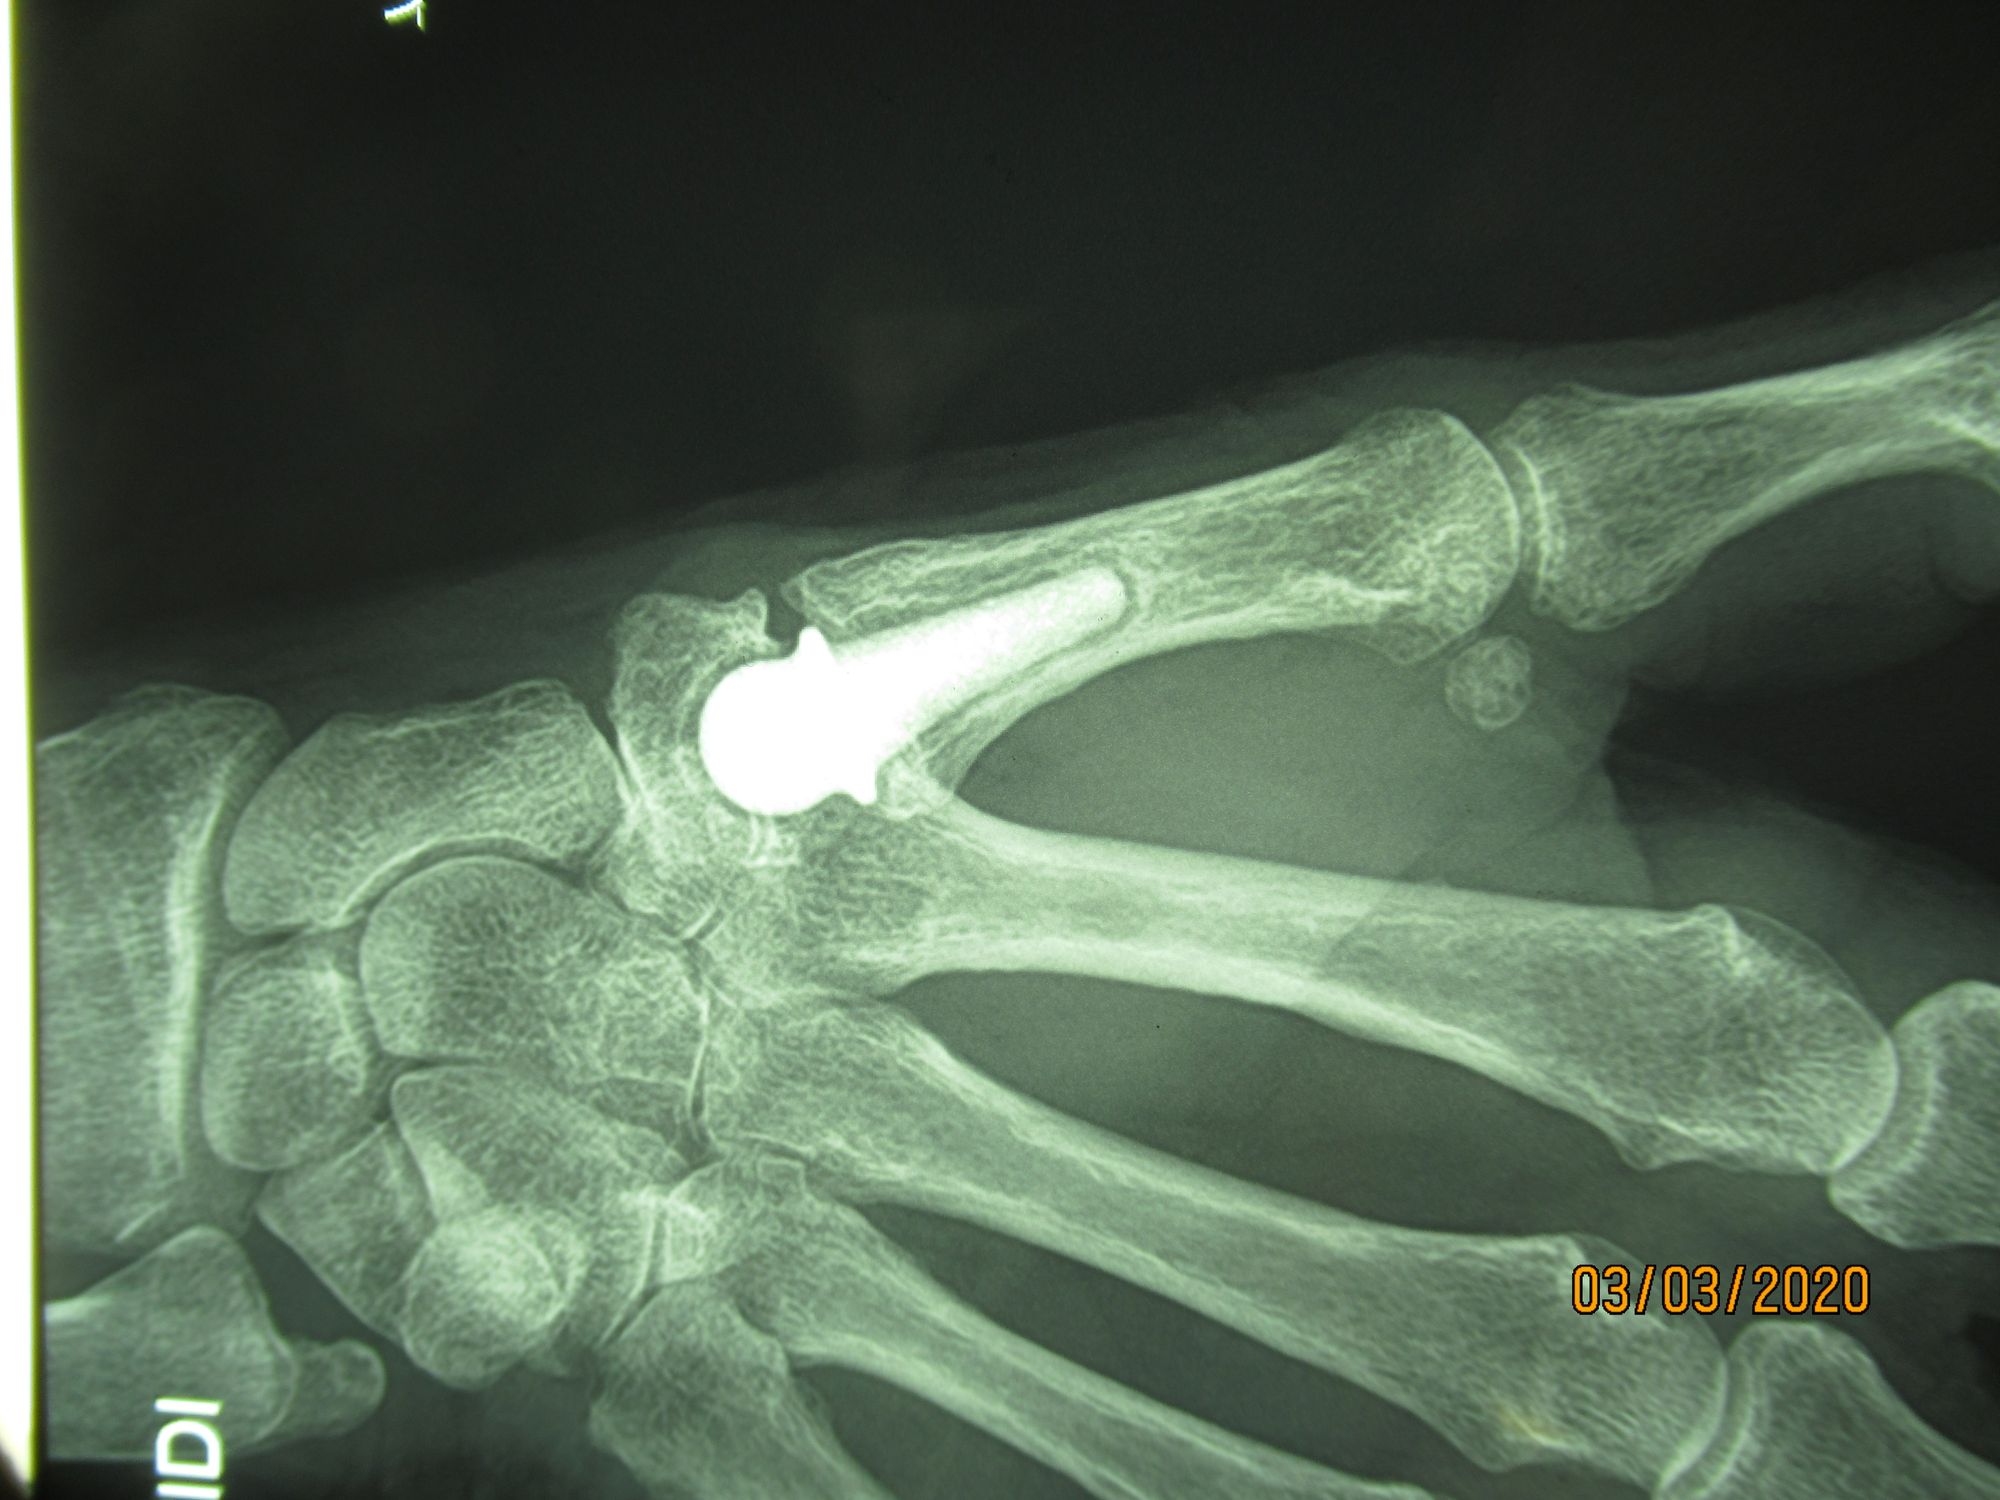

This is the perfect indication for a joint prosthesis. All implants now work, so a good outcome will depend only on choosing the right technique for the right indication in the right patient. I have had great success with a constrained prosthesis (Maia) which I show to the patient before the surgery, letting them hear the “pop” as the neck locks securely into the cup. During the actual surgery, the patients are then reassured by this familiar sound which indicates the implant is in place and perfectly stable.

Preparations for the surgery can begin well in advance of the actual procedure. The portal is created in the patient’s hand, then the radiographs are analysed to determine the location of the arthritis and how the implant will work. Selection of the right size by using x-rays with the same scale than the x-ray templates. Assessing the positioning of a Maia implant, with the stem closely following the curve of the metacarpal, running along the lateral cortex is shown in figures 8 and 9. Centred on the trapezium, the x-ray confirms that the trapezium will allow for implantation of the cup.

There are other types of implant, with single or dual mobility designs, usually designed for a cementless fit. It is hard to rank the different implants, and all series with 5 to 10 years FU report satisfactory outcomes for the designs currently on the market. Nevertheless, for dual mobility implants it is perhaps too early yet to determine their place. Supporters of dual mobility highlight the low rate of dislocation and lesser PE wear, whereas those who prefer single mobility designs argue with survivorship well beyond 10 years (17 years in one personal series using an ISIS™ implant).